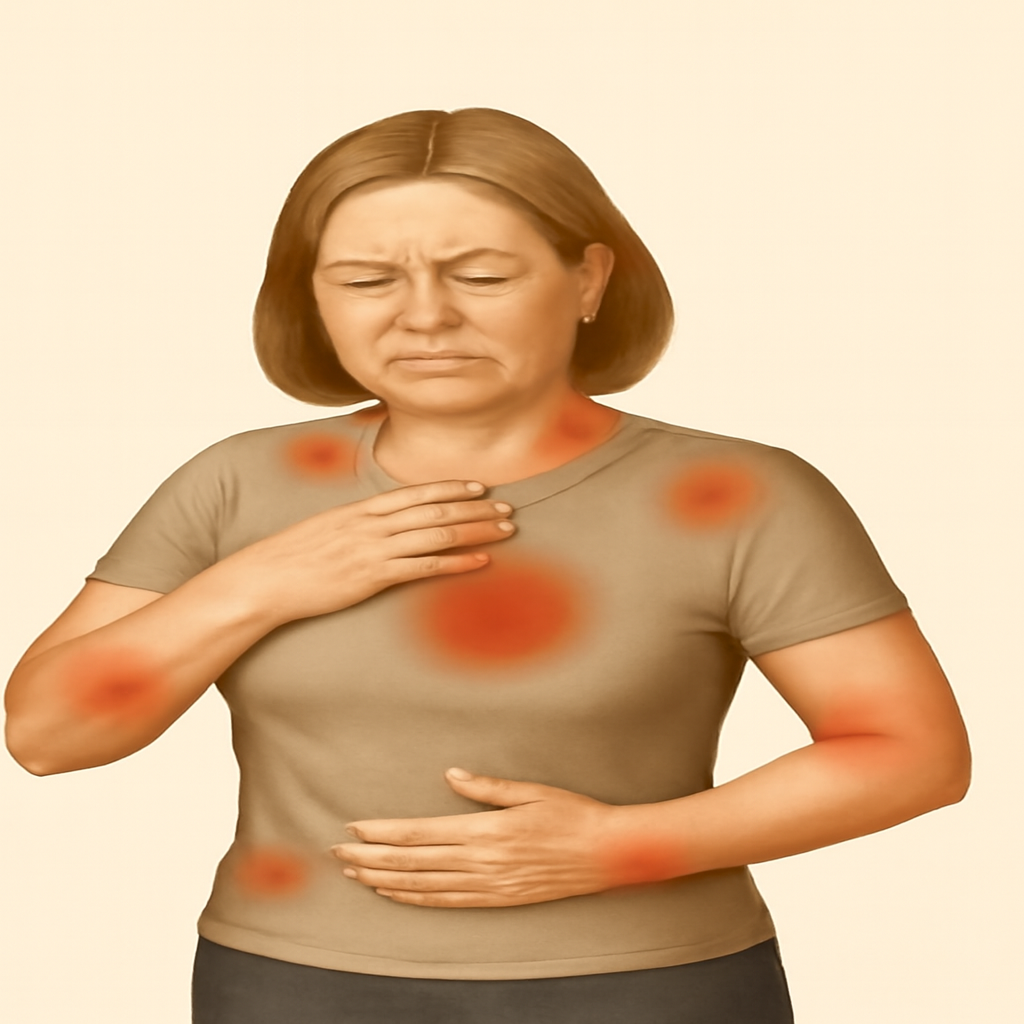

# Female

# General Medicine